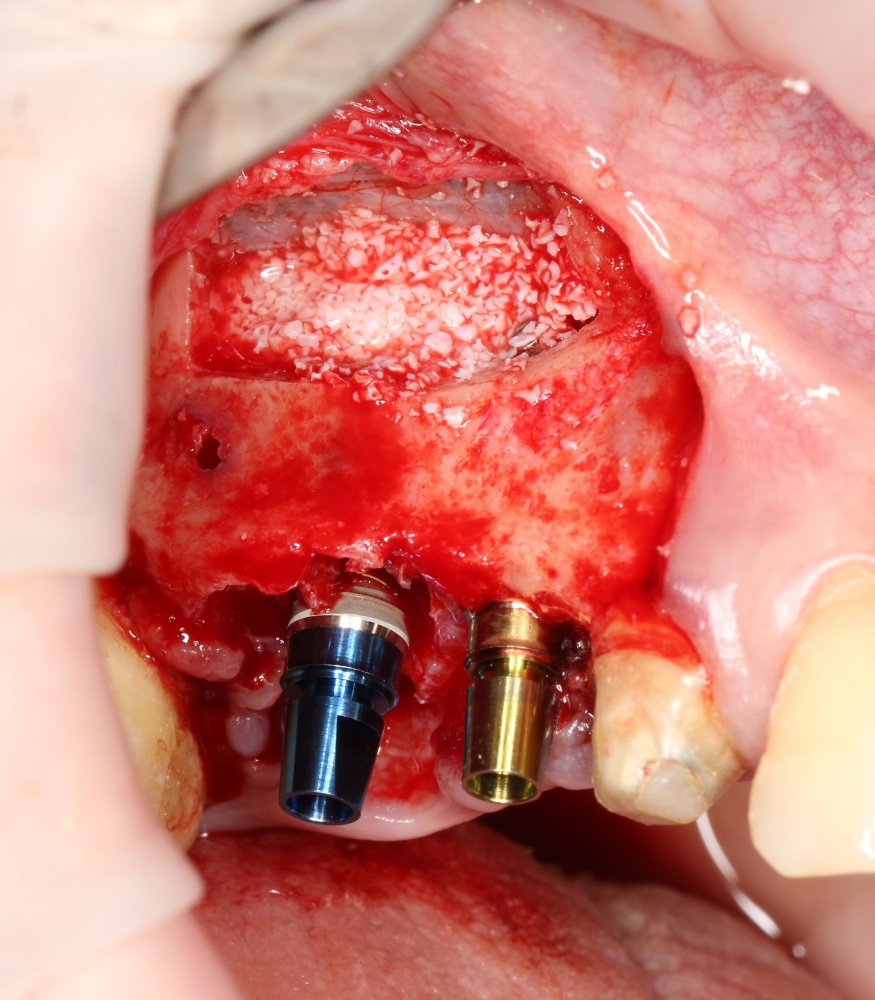

Простой синуслифтинг. Часть I.